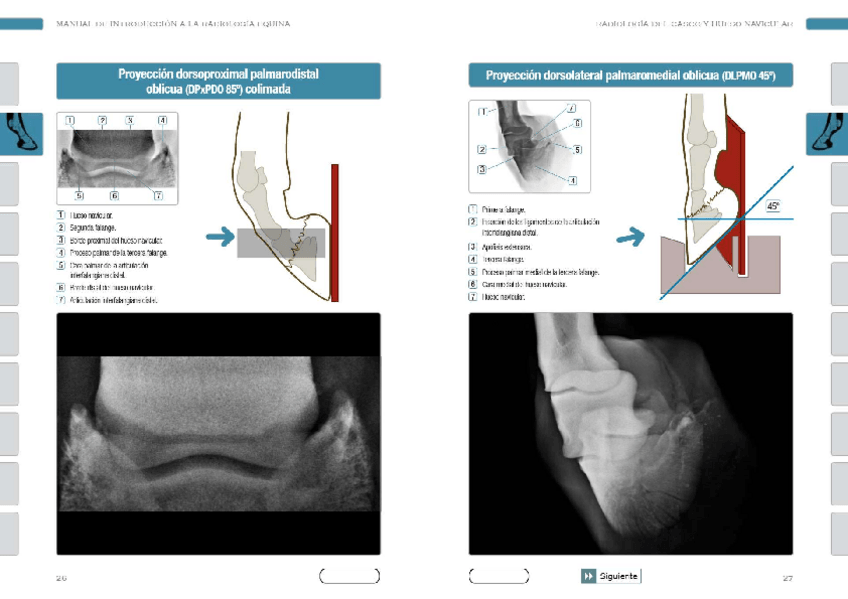

He publicado nuevos apuntes de 3º Diagnóstico Por la Imagen: Proyecciones-Radiograficas-de-menudillocanacarpo-caballo.pdf

Proyecciones.pdf